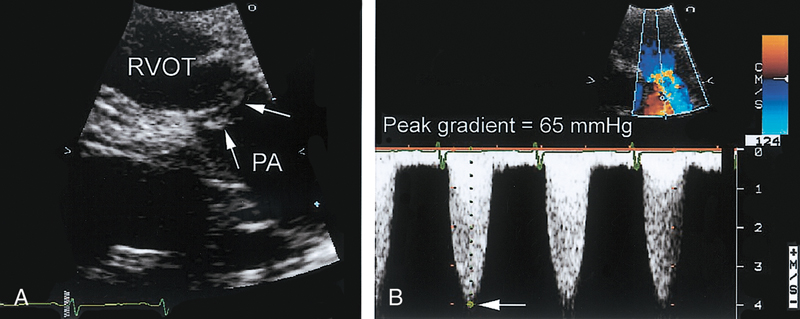

فحوصات تشخيصية لبعض امراض القلب والشرايين التاجية